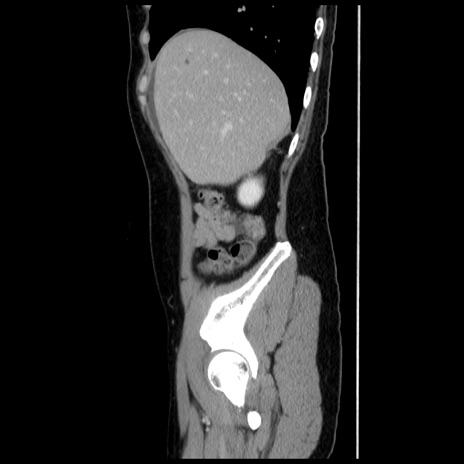

症例10(矢状断像)

【症例】 50歳代女性

【主訴】 腹痛

【現病歴】前日生レバーを食べた。今朝に排便あり。 昼前に突然発症の腹痛を生じ、当院救急外来を受診した。

【既往歴】 子宮筋腫にてで子宮全摘後

【身体所見】 意識清明、腹部:平坦、軟、下腹部やや左を中心に圧痛・反跳痛あり、筋性防御あり

【データ】WBC 7800、CRP 0.07